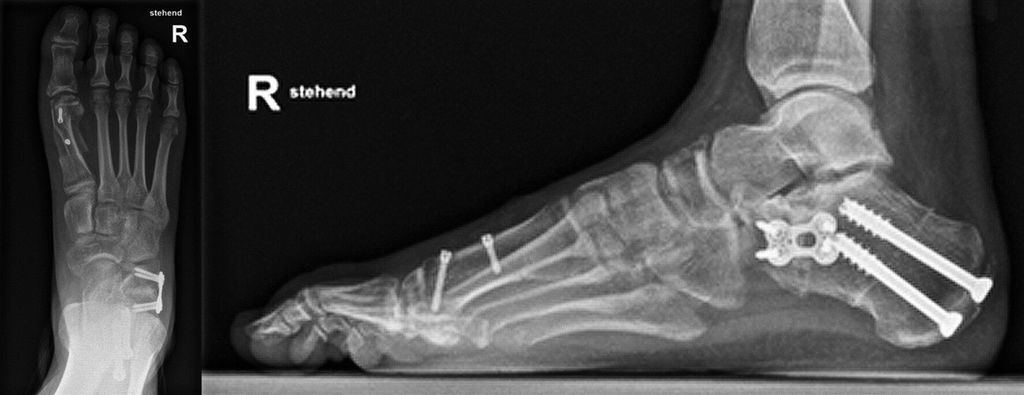

Abb. 1: Präoperativ: blaue Linie = Talus-MT1-Winkel; gebogene Linien: „talar head uncoverage“

Die Röntgenaufnahmen des Fußes und des oberen Sprunggelenks im dorsoplantaren (d.p.) und seitlichen Strahlengang erfolgen am belasteten Bein, um die Fehlstellung in ihrem vollen Ausmaß zu erfassen. Zusätzlich wird für die nativradiologische Abklärung eine Rückfußaufnahme nach Saltzman durchgeführt, in der die Valgisierung des Fersenbeines gegenüber der Tibiaachse dargestellt wird.

Die d.p. Aufnahme zeigt das Ausmaß der Abduktion des Vorfußes, die talonaviculare Überdeckung („talar head uncoverage“, Abb. 1).3 Degenerative Veränderungen der einzelnen Gelenke werden beurteilt.

Abb. 3: Calcaneusdoppelosteotomie: „lateral lengthening“ und medialisierende Verschiebeosteotomie zur Korrektur der Rückfußachse und Vorfußabduktion (Patient von Abbildung 1)